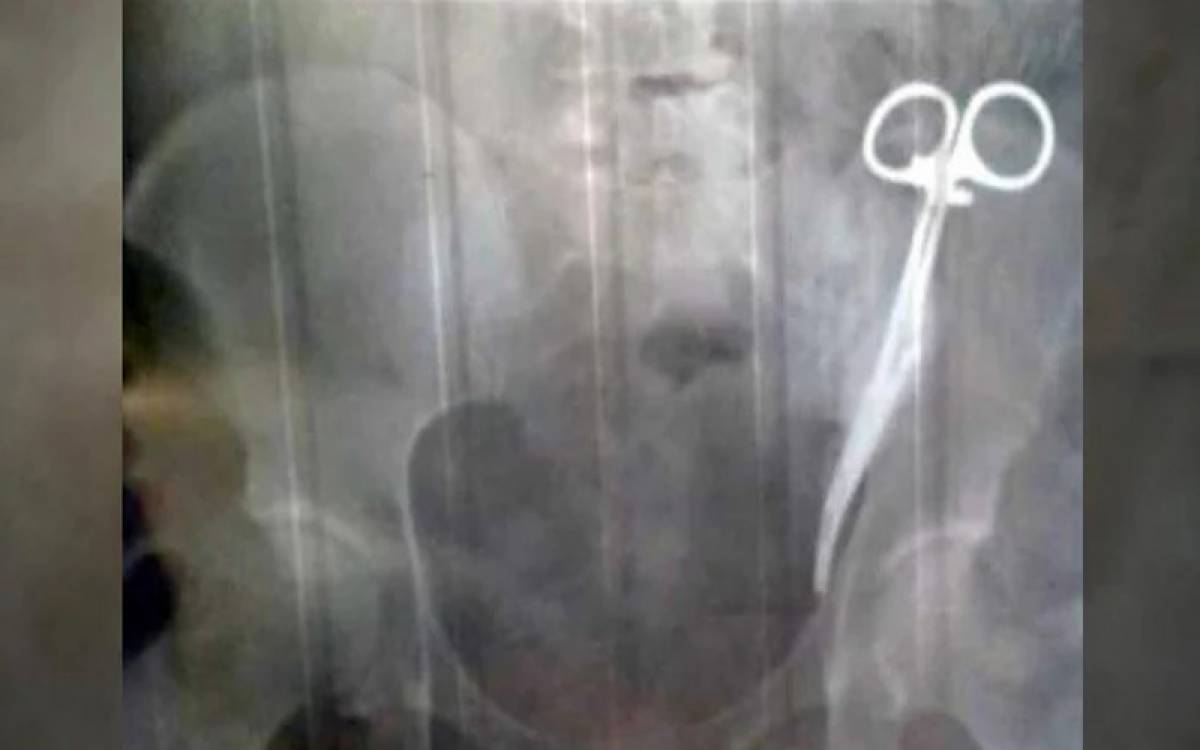

خاتون کے پیٹ سے 20 سال بعد قینچیاں نکال لی گئیں

ڈھاکا(ویب ڈیسک )بنگلا دیش میں ڈاکٹروں کی غفلت کے باعث خاتون کے پیٹ میں رہ جانے والی سرجیکل قینچیاں 20 سال بعد نکال لی گئیں۔سرجری کے وقت کیس کی نگرانی کرنے والے ایک سرجن نے ان کی تشویش کو تسلیم کرنے سے انکار کرتے ہوئے کہا کہ یہ معمول کی بات ہے، پریشان ہونے کی ضرورت نہیں،

آپ صحت یاب ہو جائیں گی۔میڈیا رپورٹس کے مطابق 55 سالہ خاتون بچینہ کا 2002 میں پتھری نکالنے کے لیے آپریشن کیا تھا تاہم اسپتال سے گھر واپس آنے کے چند روز بعد ہی اسے پیٹ میں درد ہونے لگا جس کے بعد وہ دوبارہ اسی اسپتال گئیں اور اپنی حالت بیان کی۔

جب بچینہ کے پیٹ میں درد ناقابل برداشت ہو گیا تو ایک اور ڈاکٹر کے کہنے پر اس نے اپنے پیٹ کا ایکسرے کرایا جس سے معلوم ہوا کہ اس کے پیٹ میں سرجیکل قینچیوں کا جوڑا موجود تھا جو 20 سال قبل ڈاکٹروں کی خوفناک غلطی سے بچینہ کی پیٹ میں رہ گئی تھیں۔ڈاکٹروں نے کامیاب آپریشن کر کے خاتون کے پیٹ سے قینچیوں کا جوڑا نکال لیا اور اب وہ خیریت سے ہیں۔